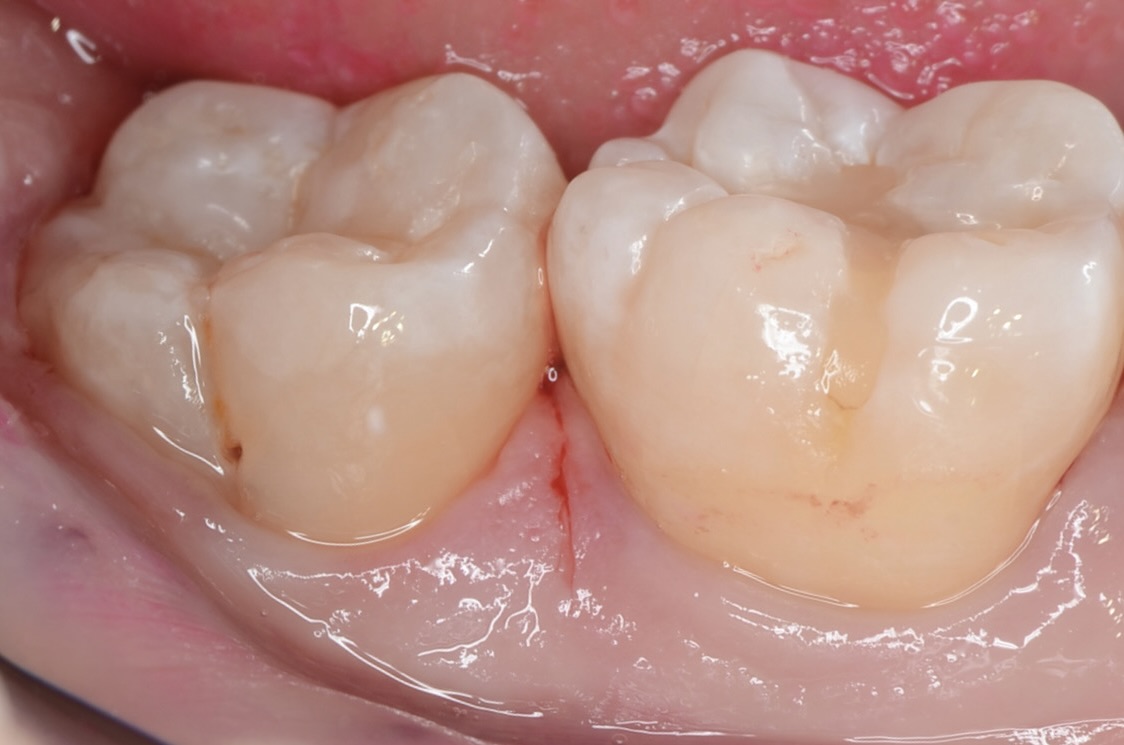

Before

側面の虫歯

細い器具で触ったところ、粘りつくような感覚がありました。中で虫歯が広がっているようです。 -